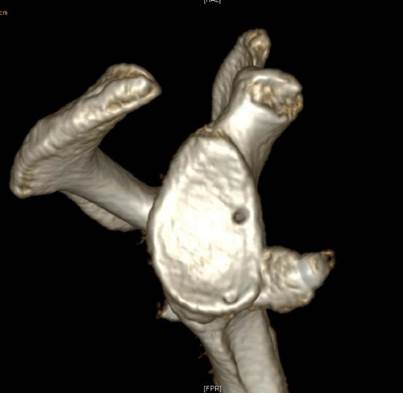

肩关节Bony-Bankart损伤

肩关节镜下缝合修复Bony-Bankart术后

近年来,开始开展全镜下喙突移位Bristow,Latarjet手术治疗肩关节复发性脱位。目前已经可以在2个小时内完成高难度的全镜下Bristow,Latarjet手术。崔国庆教授受到中国古建筑学中“榫卯”结构的启发,将之引入经典的Bristow手术中,在国际上首创关节镜下改良“嵌入式”喙突移位(Bristow)手术,并将其命名为CUIstow手术(Chinese Unique Inlay Bristow),通过增加骨接触愈合面积,显著增加了移植喙突骨块的稳定性并且极大提高了术后的骨愈合率。截至目前为止,该手术技术在课题组所在单位已经成功实施400余例,3年中期随访结果显示,术后骨愈合率达到了96.4%,并发症的发生率仅为3.6%,术后重返运动比率达到了98%,取得了非常良好的临床效果以及患者满意度。相关成果发表在国际运动医学领域权威期刊American Journal of Sports Medicine,AJSM和国际骨与关节领域权威期刊Journal of Bone & Joint Surgery,JBJS。